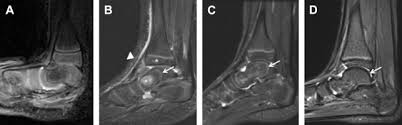

The Radiology Assistant Mri Examination Of The Ankle

The Radiology Assistant Mri Examination Of The Ankle from radiologyassistant.nl